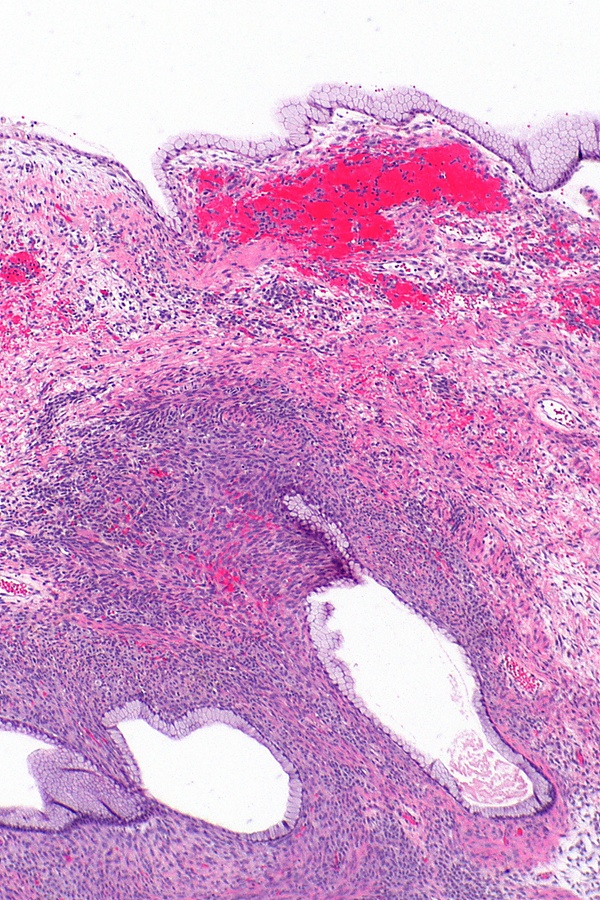

- Муцинозная цистаденома.

Многокамерное образование. Имеет капсулу, стенки которой выстилает однорядный высокий цилиндрический эпителий, также может быть кубический или уплощённый эпителий. Строма образована фиброзной тканью. Внутри заполнена муцином желтого цвета, может быть с примесью крови[8];